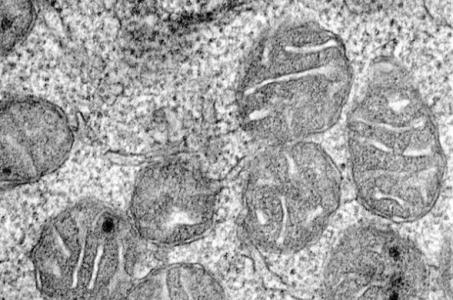

Ces cellules progénitrices érythroïdes se divisent pour fabriquer des globules rouges- mitochondries à l’intérieur de ces cellules

Les chercheurs souhaitaient comprendre pourquoi les anémies liées à une carence en fer induisent une production insuffisante de globules rouges. Ils se sont concentrés sur les cellules de moelle osseuse et y ont identifié des réservoirs importants du récepteur de l'érythropoïétine ou hormone EPO (connue pour améliorer la performance sportive), qui induit la moelle osseuse à fabriquer des globules rouges -via des cellules progénitrices érythroïdes qui se divisent pour fabriquer des globules rouges-(Visuel mitochondries à l’intérieur de ces cellules progénitrices érythroïdes). Pour accomplir sa fonction de fabrication des cellules sanguines, le récepteur doit être à l'extérieur des cellules médullaires et pourtant les chercheurs constatent ici ces quantités importantes stockées à l'intérieur des cellules.